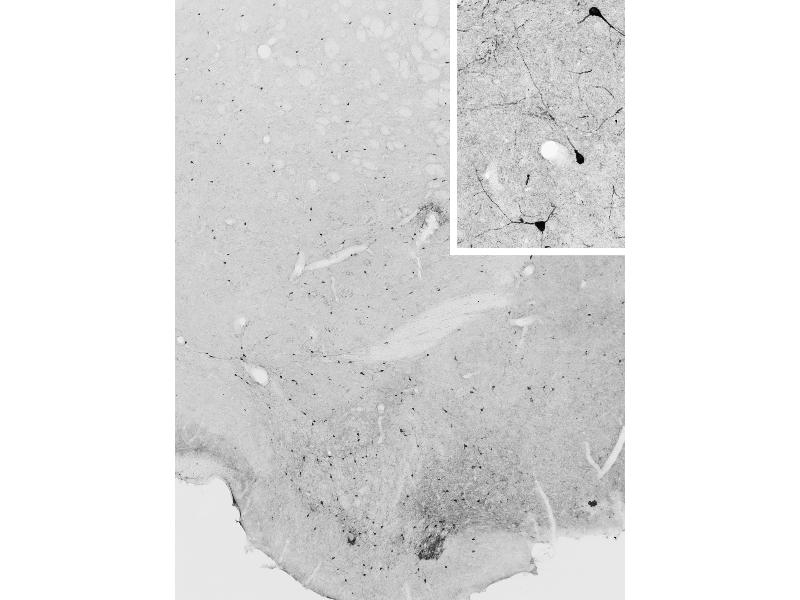

L'immunohistochimie (IHC) désigne le processus de détection des antigènes dans les cellules d'une coupe de tissu en exploitant le principe de liaison spécifique des anticorps aux antigènes des tissus biologiques. Elle est largement utilisée dans le diagnostic des cellules anormales comme celles que l'on trouve dans les tumeurs cancéreuses et dans la recherche fondamentale pour comprendre la distribution et la localisation des biomarqueurs et des protéines exprimées de manière différentielle dans différentes parties d'un tissu biologique. Visualiser une interaction anticorps-antigène peut être accompli de plusieurs façons. Dans le cas le plus courant, un anticorps est conjugué à une enzyme, comme la peroxydase, qui peut catalyser une réaction produisant une couleur, ou marqué à un fluorophore.